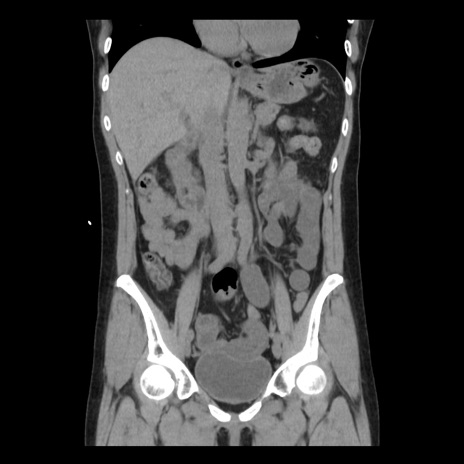

症例10(冠状断像)

【症例】 50歳代女性

【主訴】 腹痛

【現病歴】前日生レバーを食べた。今朝に排便あり。 昼前に突然発症の腹痛を生じ、当院救急外来を受診した。

【既往歴】 子宮筋腫にてで子宮全摘後

【身体所見】 意識清明、腹部:平坦、軟、下腹部やや左を中心に圧痛・反跳痛あり、筋性防御あり

【データ】WBC 7800、CRP 0.07